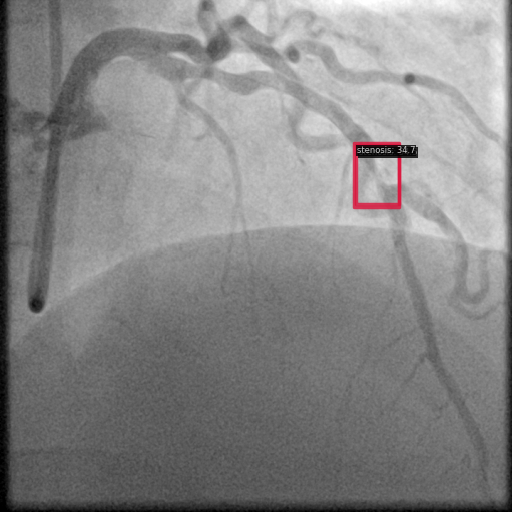

To further assess the detection performance, qualitative results for three test images are presented in Figure 2. The first column shows the original images with ground truth annotations. The second, third, and fourth columns depict detections from DINO-DETR, Grounding DINO, and YOLO, respectively.

(a) Original (b) DINO-DETR (c) Grounding DINO (d) YOLO

The qualitative comparison in Figure 2 reinforces the trends observed in the quantitative evaluation. DINO-DETR produced fewer detections, occasionally missing relevant stenotic regions, consistent with its conservative detection strategy aimed at minimizing false positives [6]. Grounding DINO, although capable of identifying more regions, sometimes resulted in cluttered predictions due to over-detections [7]. YOLO provided a reasonable trade-off by effectively capturing anatomical structures while maintaining relatively high confidence scores and clear visualizations [5].